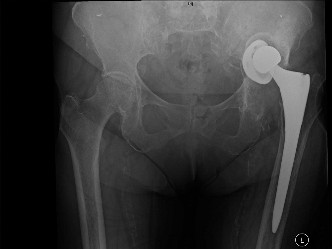

A 79-year-old female with a history of a left total hip replacement performed 10 years ago presents with wors…